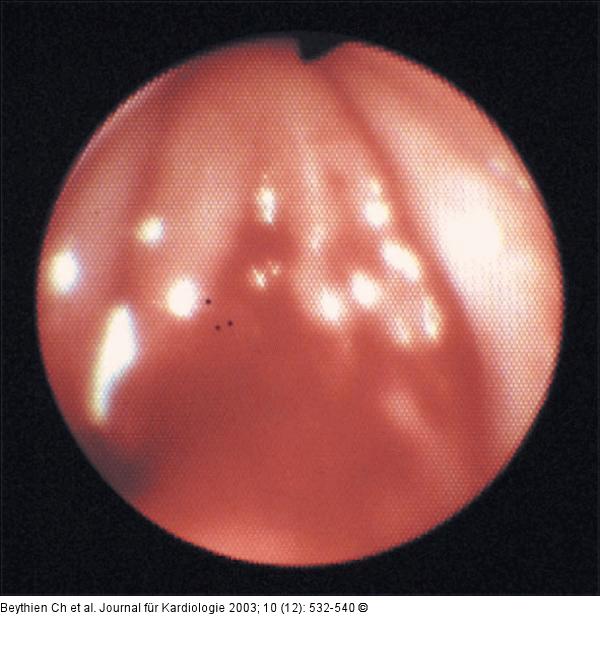

Abbildung 12: Stimmbänder - Schleimhautläsion Endoskopischer Blick auf die Stimmbänder mit Demonstration deutlicher Schleimhautläsionen an der Basis. |

Abbildung 12: Stimmbänder - Schleimhautläsion

Endoskopischer Blick auf die Stimmbänder mit Demonstration deutlicher Schleimhautläsionen an der Basis. |